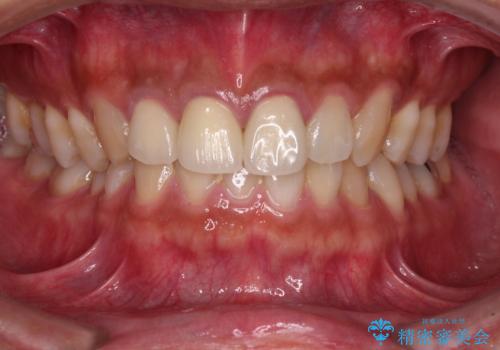

銀歯を白くしたい

- 数年前他院にて治療した銀歯をやり替え希望の患者様です。

拡大鏡下で、銀歯、むし歯の除去を行い、セラミックインレーに適した形に整えました。

精度の良いインレーを製作するために、シリコーンにて型どりしました。

また確実な接着操作を行うために、インレーを接着する際にはラバーダム防湿を行いました。

銀歯を気にせずに笑うことができると満足していただきました。